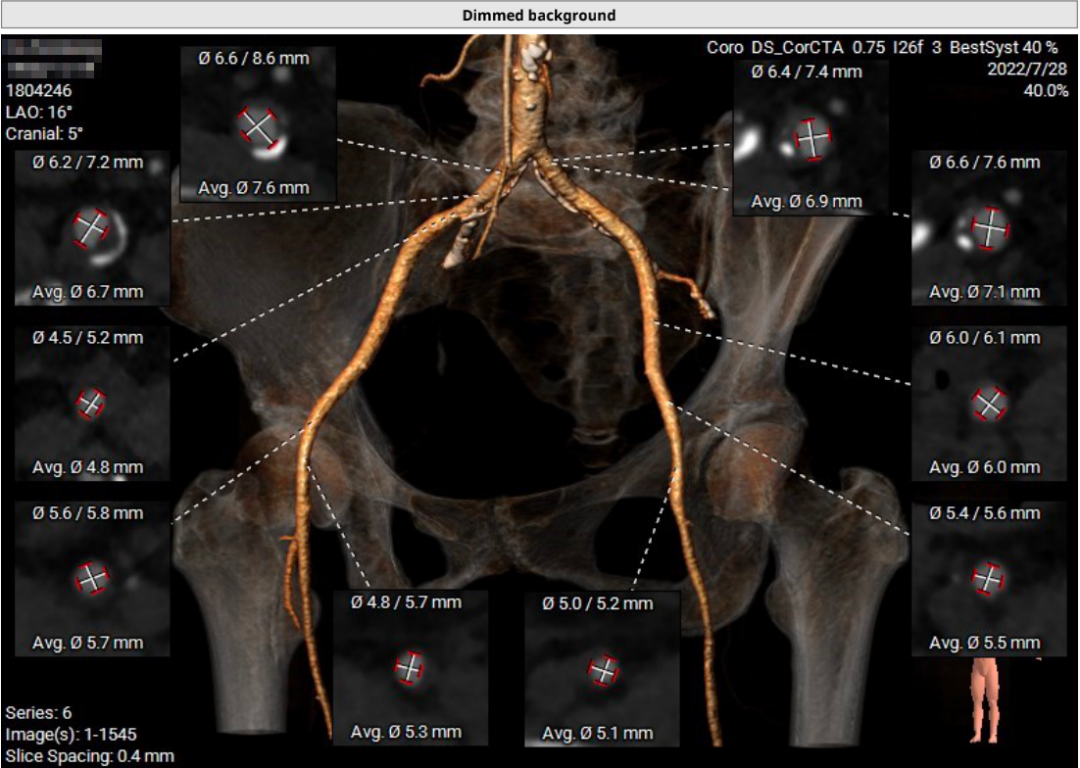

患者64岁男性,Type 0 型二叶瓣、横位心。主动脉瓣中度狭窄,重度反流,瓣环周长92.0mm,平均径29.0mm。LVOT周长98.7mm,升主扩张,窦部结构极限,锚定能力极限。入路两侧血管轻度迂曲,分叉高度可,两侧血管内径均>8mm。

患者左、右冠高度,瓣叶长度,窦宽相对瓣膜均尚可,冠脉风险低。但由于患者重度AR,可能因植入深度和选择大型号瓣膜,带来较高的传导阻滞风险。其次,患者升主扩张,存在破裂风险。最后,患者是横位心,瓣环及流出道结构大,术中瓣膜释放的位置达到了极限,瓣膜释放后可能会发生位移,有瓣中瓣风险。

首先,最重要的是观察瓣环结构,理论上如果瓣环周长超过85mm,尽量就不做;第二,看流出道情况,最好是直筒状的,瓣环和瓣下4mm的直径比值,理论上不能超过1:1.1,如果超过1.1以上就变成喇叭状,也不建议做;第三,避免存在升主动脉显著扩张,如果扩张明显,无法提供有效的锚定。总体来说,最主要的一定是瓣环直径,瓣叶有没有增厚,瓣叶有没有钙化,瓣环能否有效固定住植入的瓣膜。瓣环的固定和锚定条件,是反流患者能否进行TAVR的决定因素。